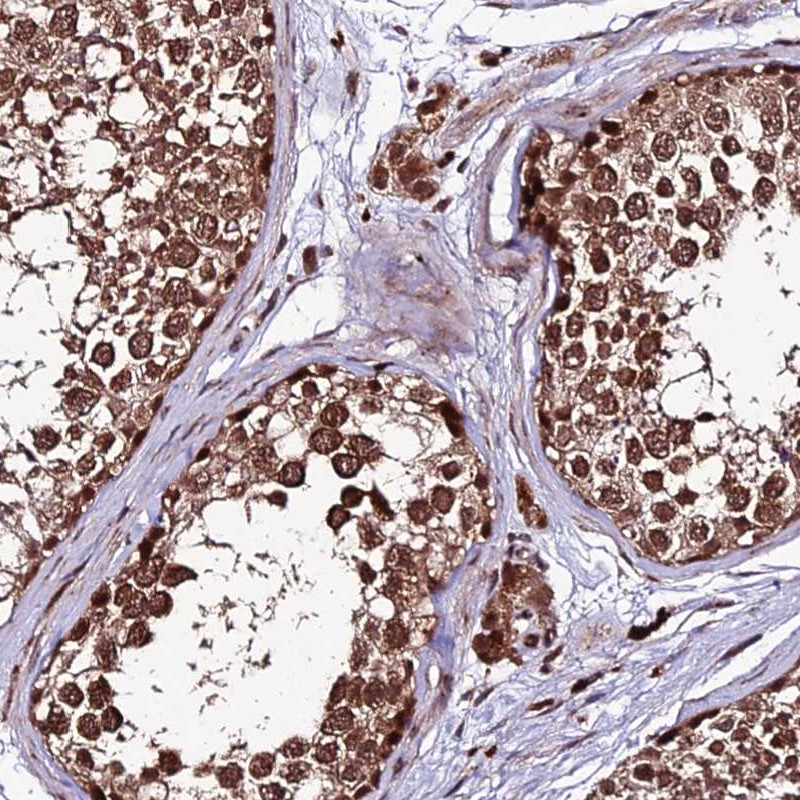

Immunohistochemical staining of human testis shows strong cytoplasmic and nuclear positivity in cells of seminiferus ducts.